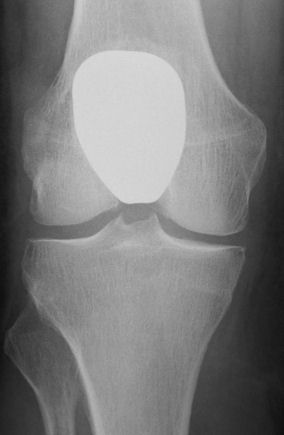

Front view showing the resurfacing of the front of the thigh bone with a cobalt chrome alloy Sigma component .